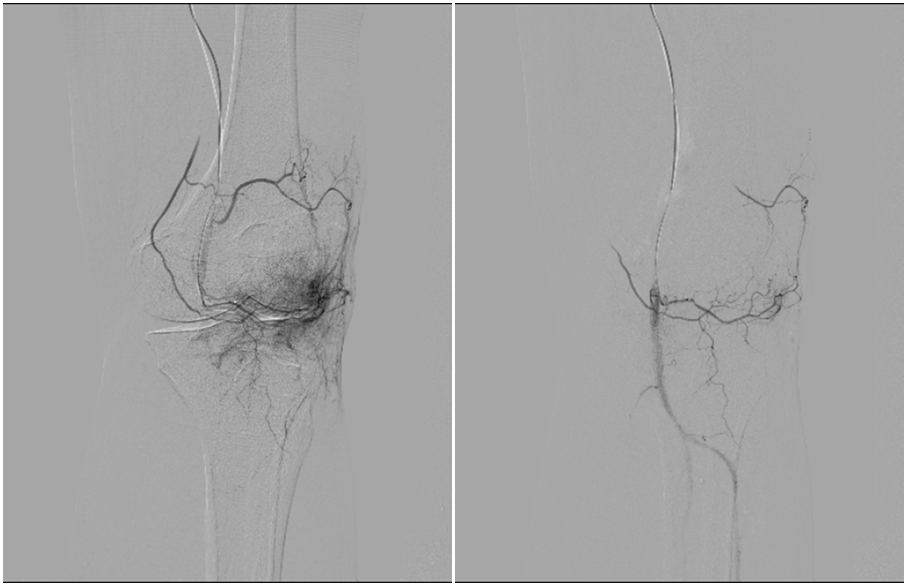

“我们通过在患者大腿根部的微小穿刺点,将导管送至膝关节的病变血管处。”朱永强指着显示屏上的影像说,病变血管网络在影像下会呈现为异常染色的“云雾状”区域,这些就是炎症的根源。他们通过栓塞精准切断异常血管的血供,从源头消除炎症。

术前左膝关节造影可见异常染色(左图)栓塞后异常染色消失(右图)